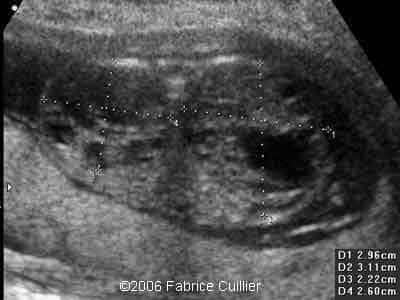

2D parasagittal view at 17 weeks

2